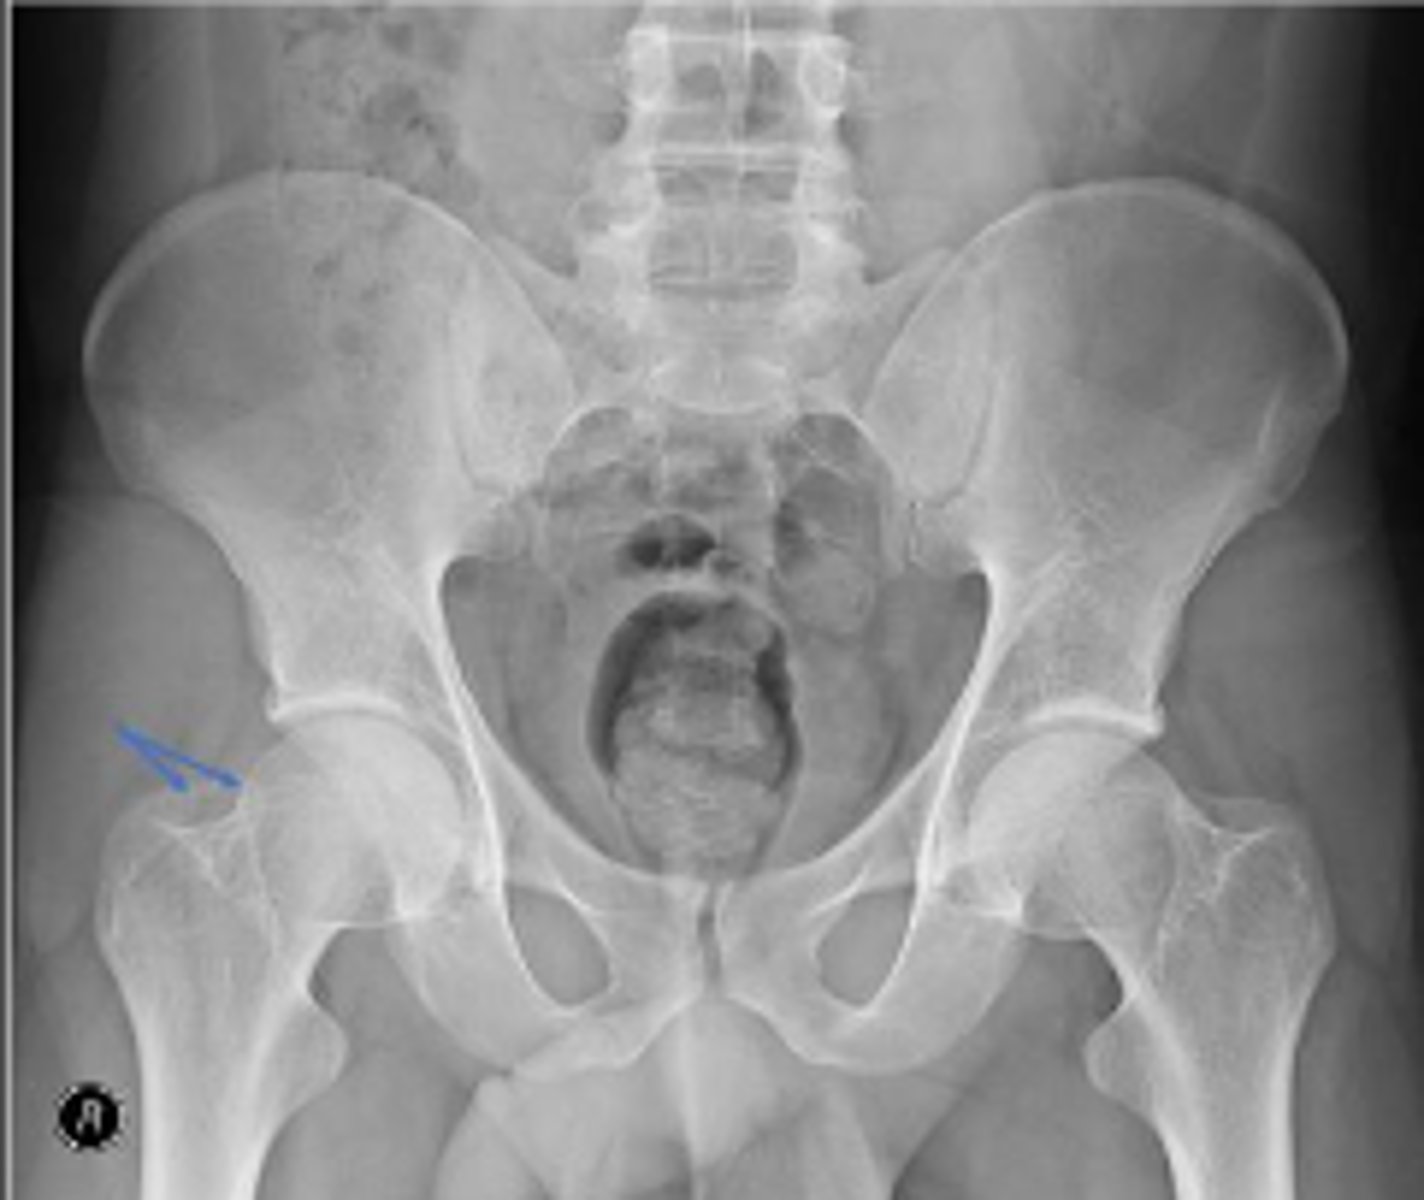

Right AP hip

What is the name of the radiographic view?

Posterior rim of the right acetabulum

What are the arrows pointing to?

Anterior rim of the right acetabulum

Lesser trochanter of the right femur

Greater trochanter of the right femur

Intertrochanteric line of the right femur